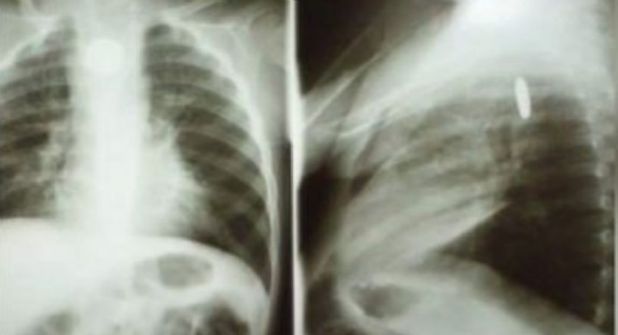

HERMOSILLO.- Un pequeño de nombre Dylan se encuentra luchando por su vida luego de haberse tragó por accidente una pila, la cual le ha provocado daños en el esófago y pulmones. El niño de dos años de edad esta hospitalizado en el área de terapia intensiva del Hospital Infantil del Estado de Sonora (HIES) desde el pasado 27 de octubre.

Ante la gravedad de su estado de salud, Dylan fue trasladado al Hospital Infantil del Estado Sonora donde su estado de salud es reservado, la pila reventó en el interior de su organismo provocando quemaduras en su estómago e infección en un pulmón, por lo que requiere que se le hagan estudios constantes, los cuales tiene un costo elevado, ante ello familiares del pequeño, quien es originario de Cananea lanzaron una campaña de apoyo mediante sus redes sociales debido a que la atención médica está resultando costosa, por lo que buscan recabar fondos que les ayuden a sostener los gastos hospitalarios.

Nayeli comentó que a 12 días de este trágico acontecimiento Dylan no han podido ser operado por que su sangre no esta generando oxigeno.